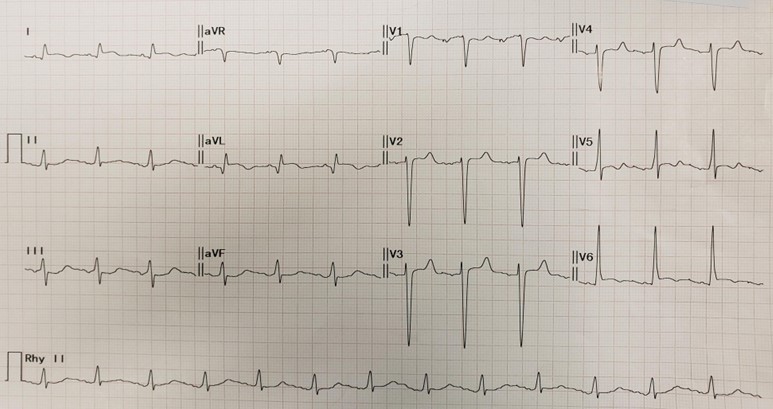

Blood tests revealed a markedly elevated high-sensitive troponin I level to more than eight thousand.Transthoracic echocardiogram showed concentric left ventricular hypertrophy changes with a normal left ventricular systolic function without regional wall motion abnormalities.ECG showed LVH pattern changes with non-specific dynamic T wave changes.